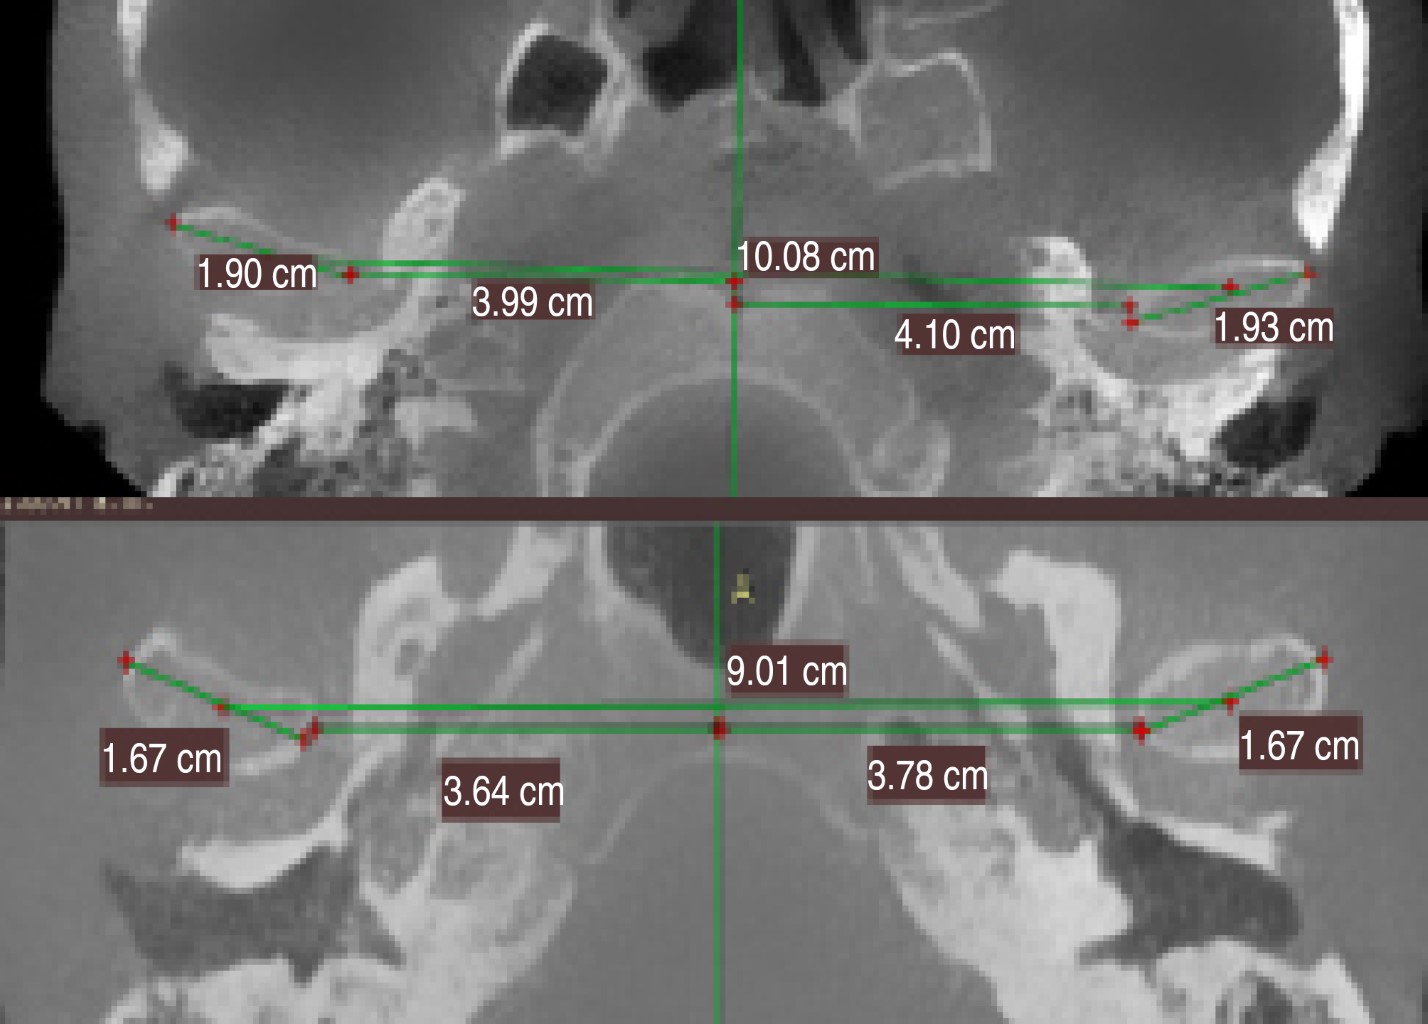

CORTE AXIAL: UNA LíNEA PARAMEDIANA DE REFERENCIA SE DIBUJó PASANDO POR EL TABIQUE NASAL Y EL CENTRO DEL FORAMEN OCCIPI- TAL, OTRA LíNEA TRANSVERSAL, TANGENTE EN EL CóNDILO. LUEGO SE MIDIERON LOS SIGUIENTES PARáMETROS: DISTANCIA INTERCONDILAR (DI: DISTANCIA ENTRE LOS DOS CóNDILOS MEDIDOS SOBRE LA LíNEA TANGENTE TRANSVERSAL); DISTANCIA CONDILAR DERECHA (DCD: DISTANCIA ENTRE EL CENTRO DEL CóNDILO DERECHO Y LA LíNEA DE REFERENCIA PARAMEDIANA); DISTANCIA CONDILAR IZQUIERDA (DCI: DISTANCIA ENTRE EL CENTRO DEL CóNDILO IZQUIERDO Y LA LíNEA DE REFERENCIA PARAMEDIANA); LONGITUD CONDILAR DERECHA (CD); LONGITUD CONDILAR IZQUIERDA (CI). (FIGURA 1)

En relación a las mediciones realizadas de las distancias intercondilares (DI) se evidenció la existencia de diferencias significativas en la distancia intercondilar (a nivel total) prome- dio (Tabla 8): lado derecho e izquierdo de los pacientes que fueron objeto de osteotomía bimaxilar p= 0.012, es decir, p < 0.05), lo que se correlaciona con el aumento del espacio articular medial (Tabla 9)

En sentido latero-medial, los desplazamientos no son reproducibles. Las ATM son estructuras que operan juntas, unidas por un solo hueso; sin embargo, ellas pueden estar sujetas a diferentes cantidades de estrés, que puede resultar en un proceso de remodelación ósea específica para cada cóndilo. En dos casos se evidenció la existencia de diferencias significativas en la distancia intercondilar (a nivel total) promedio: lado derecho e izquierdo de los pacientes que fueron objeto de osteotomía bimaxilar (p = 0.012, es decir, p < 0.05), lo que se correlaciona con el aumento del espacio articular medial.

• 2. Se evidenciaron cambios importantes en las mediciones transversales evaluadas en el corte axial de las tomografías en el grupo de pacientes sometidos a cirugía bimaxilar. Un aumento de la distancia intercondilar rechaza la hipótesis nula de que no hay diferencias en las medidas preoperatorias y postoperatorias de la misma. Estos valores arrojados coinciden con el aumento del espacio articular medial (EAM).